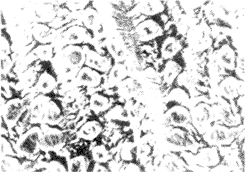

2.5 自体静脉间置后超微结构改变 自体静脉呈动脉样改变,可见少数残存的内皮细胞,胶原纤维,弹力纤维丰富(图4A,B)。

图4 静脉电镜扫描(×1 500)

Fig 4 Scanning electromicroscopy of veins(×1 500)

, 百拇医药

A: Normal; B: Interpositional